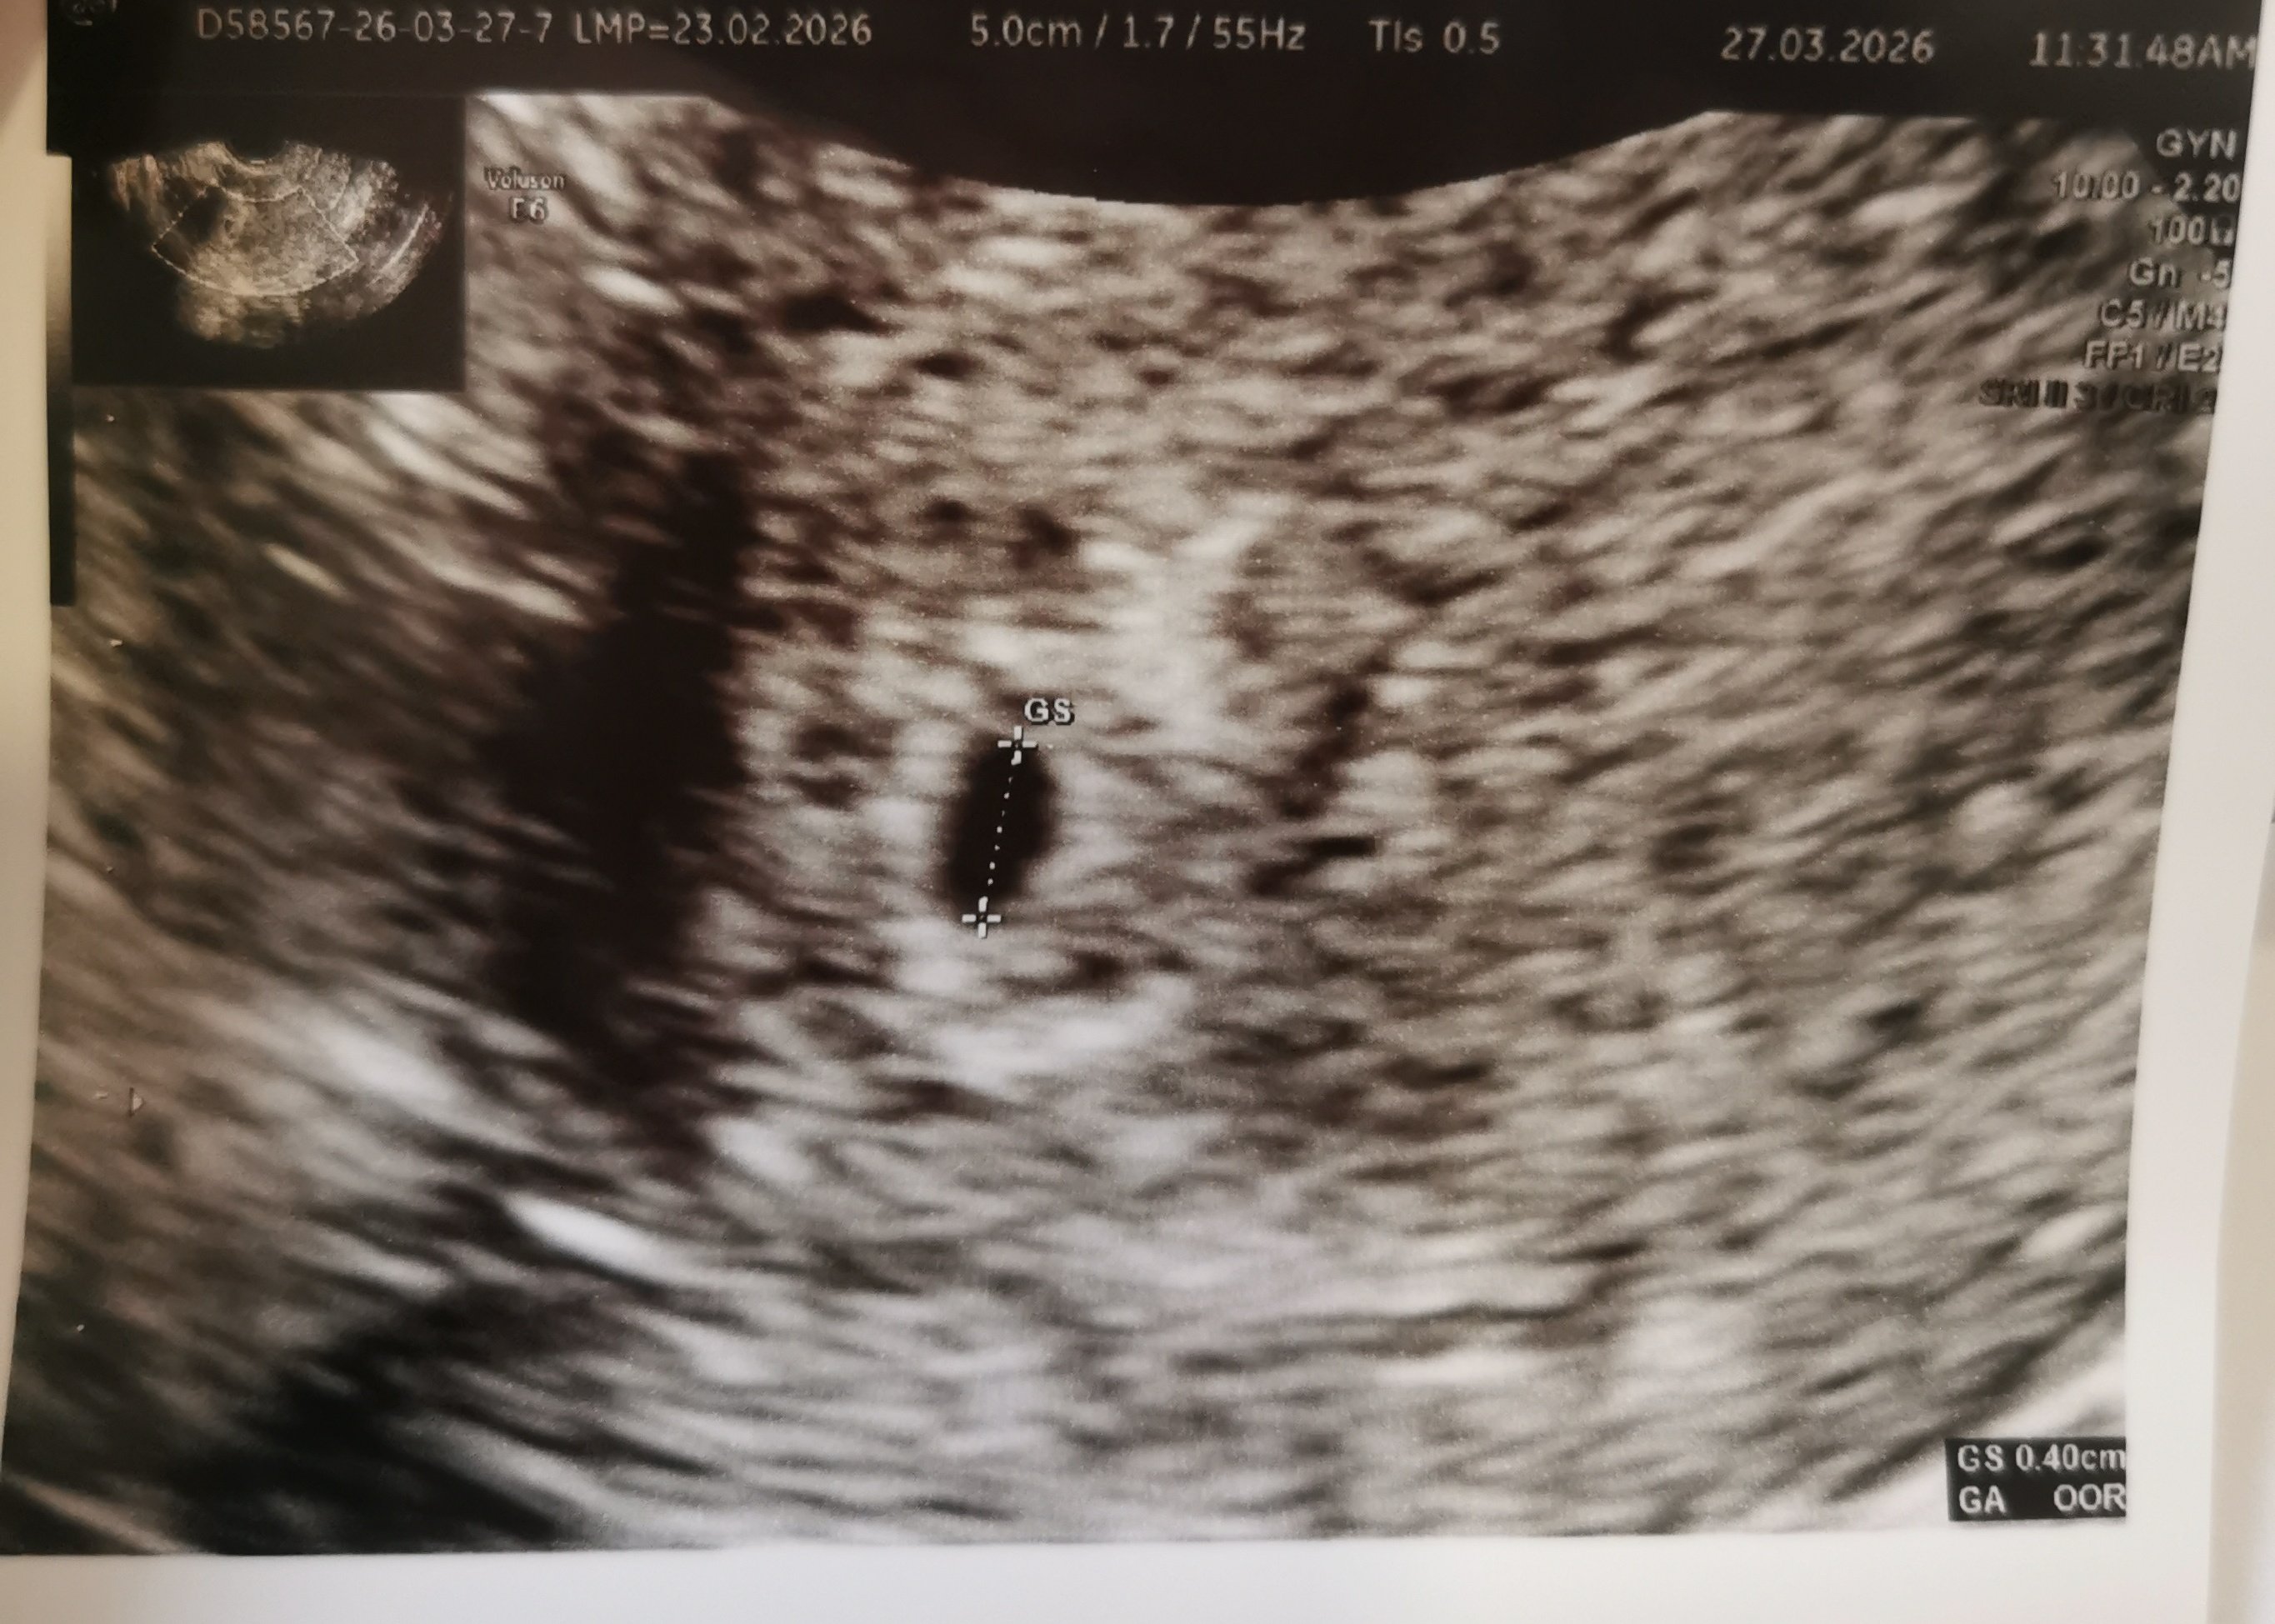

Widzę że jest pęcherzykDziewczyny ja już po pierwszym USGmamy kropeczkę całe 4mm

umiejscowiona prawidłowo, żadnych nieprawidłowości w tej chwili poza torbielą na jajniku ale to pojawia mi się co jakiś czas

tak się cieszę

Taaak, jestem dziś dopiero 4+5 więc i tak się cieszę że cokolwiek zobaczyliśmyRodziłam tam i drugi raz bym się tam nie zdecydowała a Twoje słowa mnie tylko w tym bardziej utwierdziły.

Widzę że jest pęcherzykwczesne USG , za tydzień pewnie będzie coś więcej